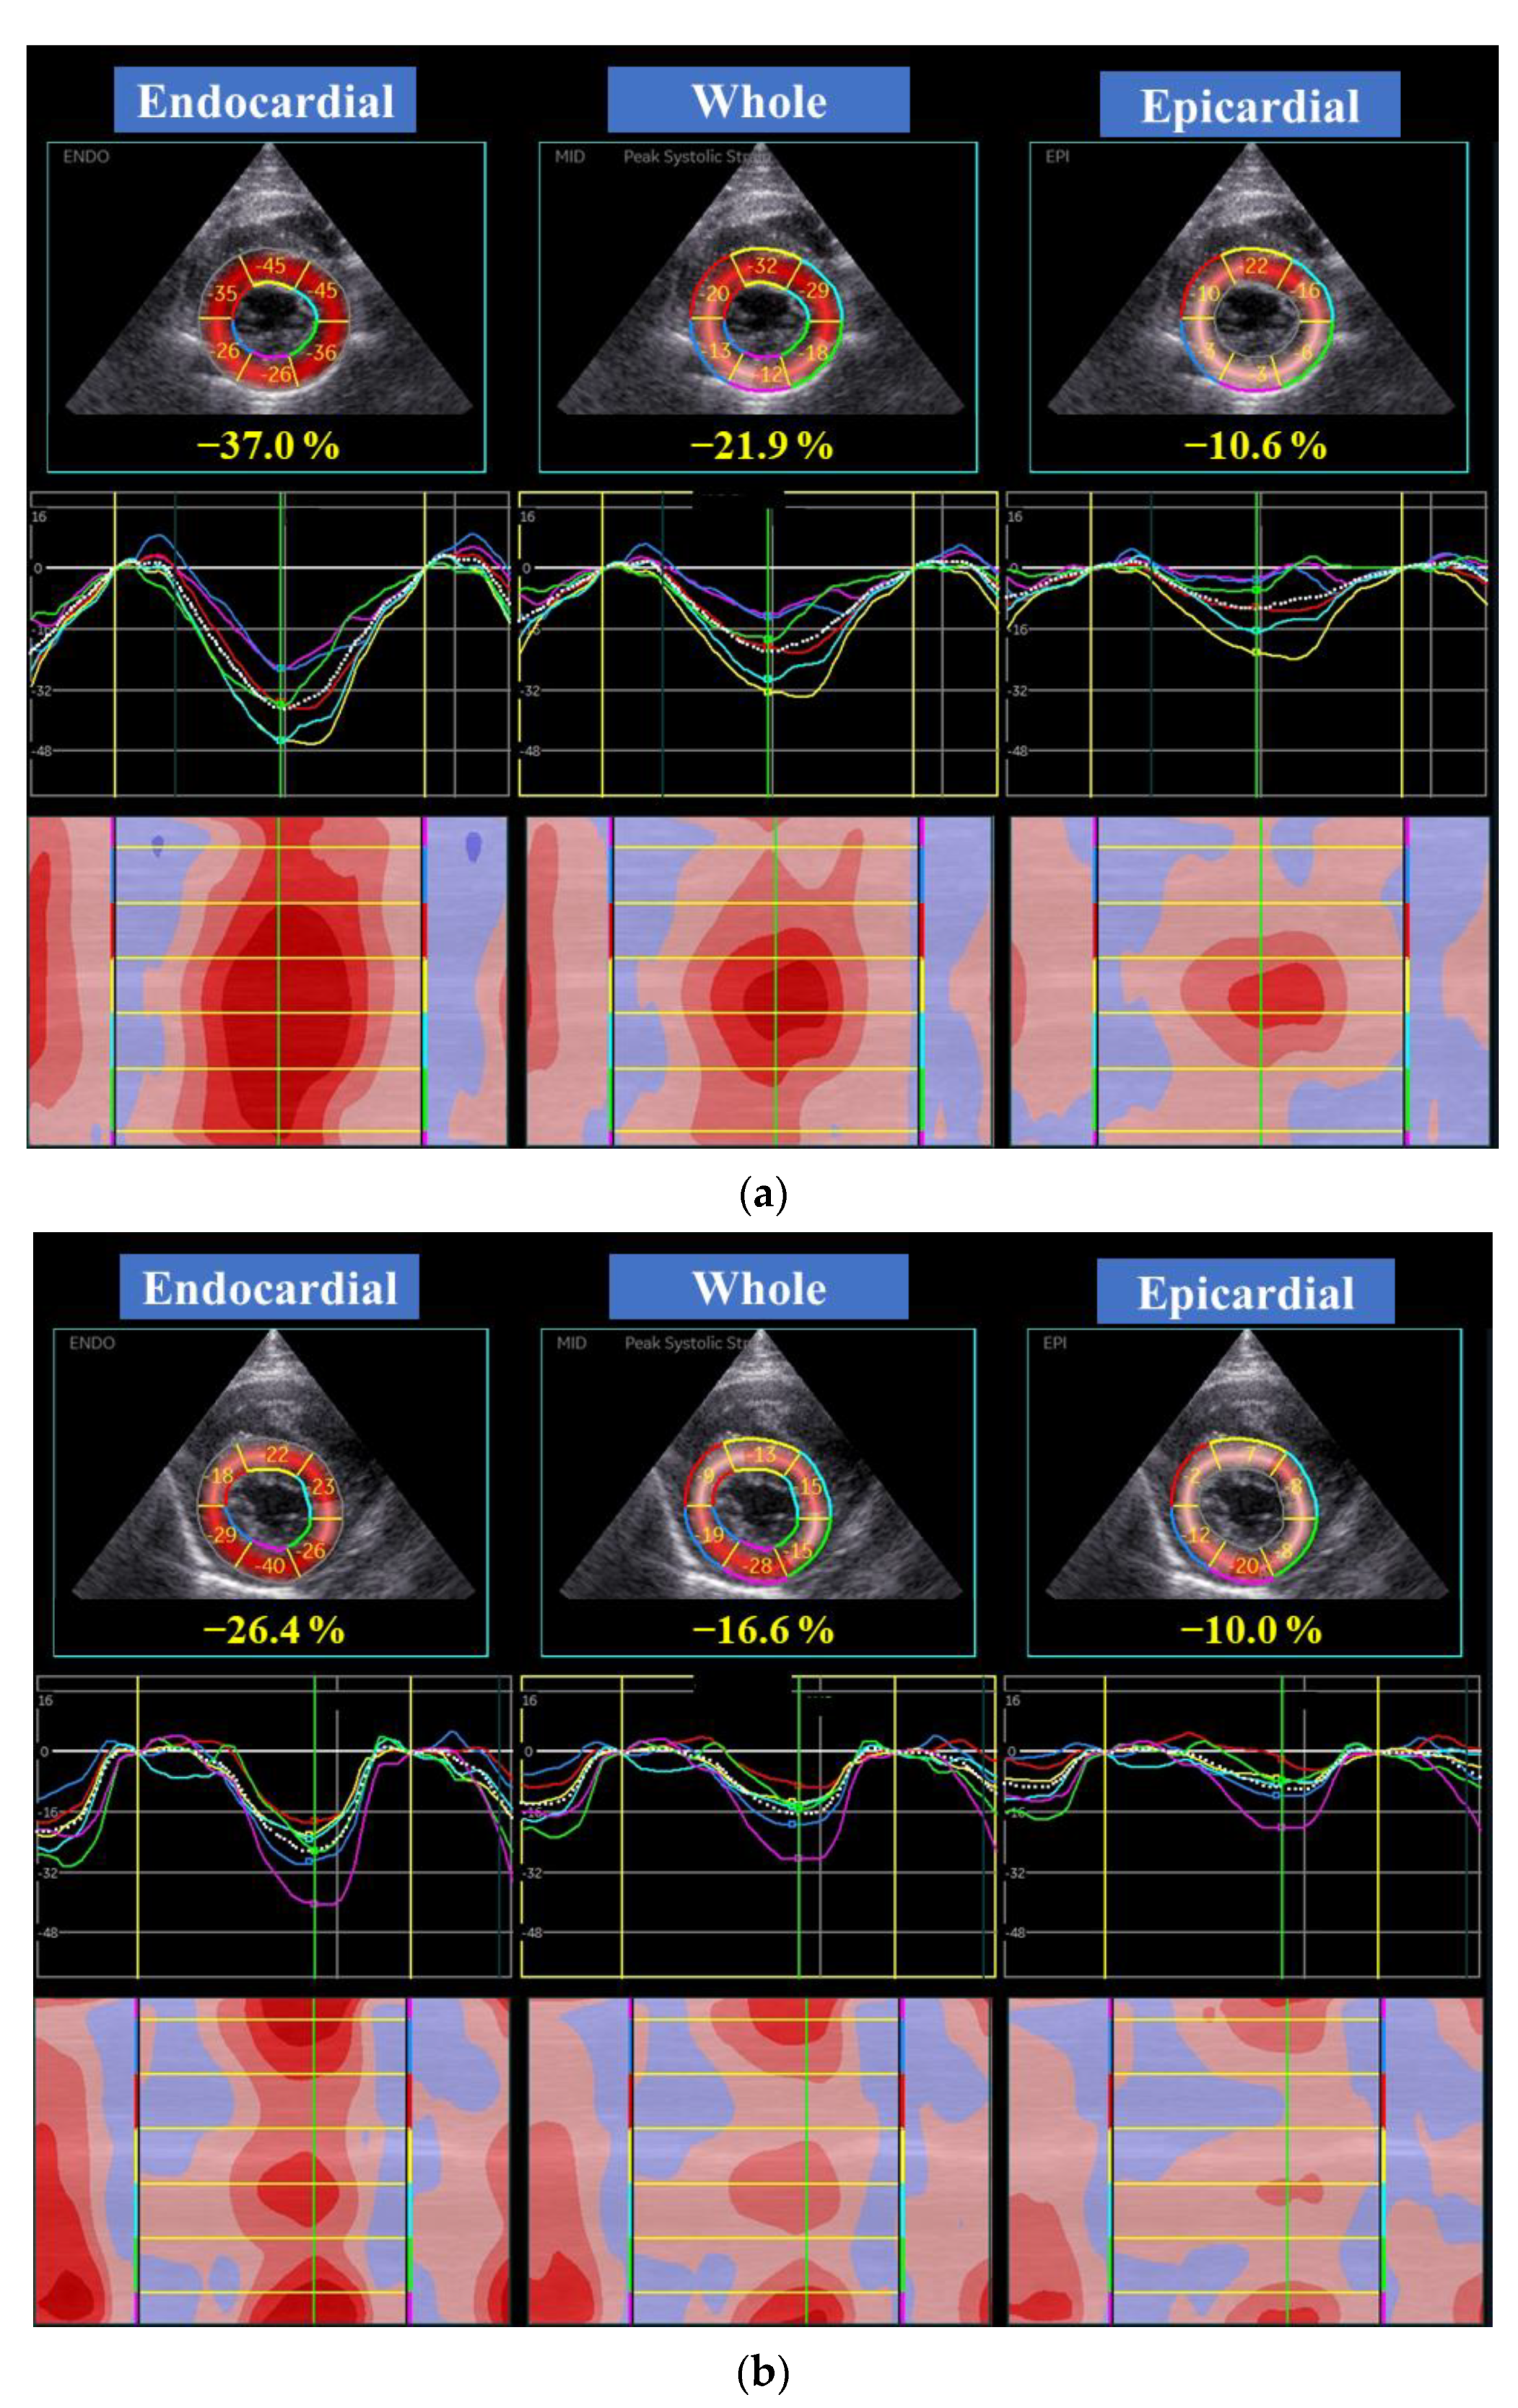

| Global LV circumferential strain (%) | |||||||

| Whole layer | 17.4 | (15.4, 21.3) | 10 | 19.1 | (17.3, 23.9) | 15 | 0.09 |

| Endocardial layer | 27.7 | (25.4, 32.6) | 10 | 38.7 | (32.7, 48.3) | 15 | <0.01 |

| Epicardial layer | 10.4 | (8.5, 12.3) | 10 | 7.3 | (6.2, 9.3) | 15 | 0.14 |

| Endo/Epi | 2.73 | (2.08, 4.06) | 10 | 4.77 | (4.12, 6.50) | 15 | <0.01 |